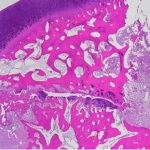

トイプードルの無菌性大腿骨頭壊死(レッグ・カルベ・ペルテス病)

レッグカルべペルテス病について 大腿骨頭および骨頚の無菌性壊死症が起こる疾患です。 大腿骨頭の虚血性壊死が原因で海綿骨が微小骨折し、痛みを伴います。 ・疫学 小型犬および超小型犬に発生します